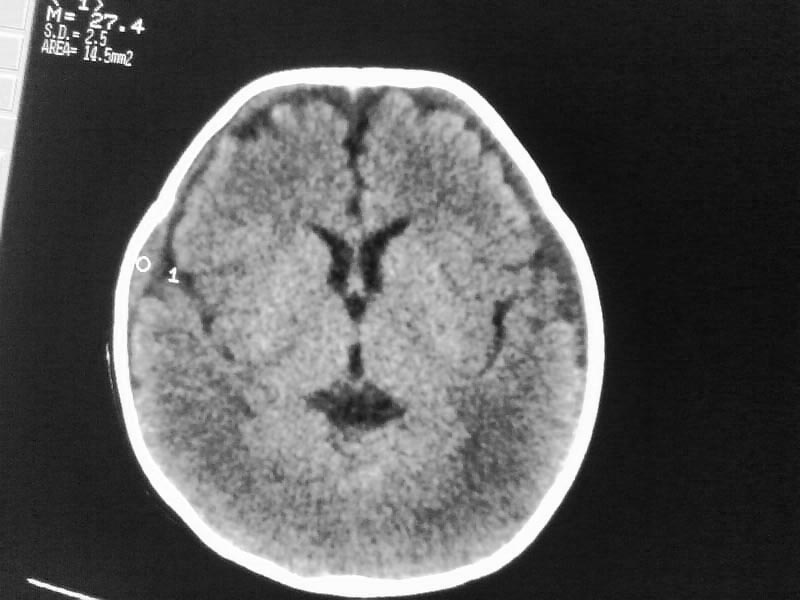

以下是引用随光逐影在2009-4-15 17:59:00的发言:[br]1)右侧额颞顶部硬膜下血肿。2)外部性脑积水。